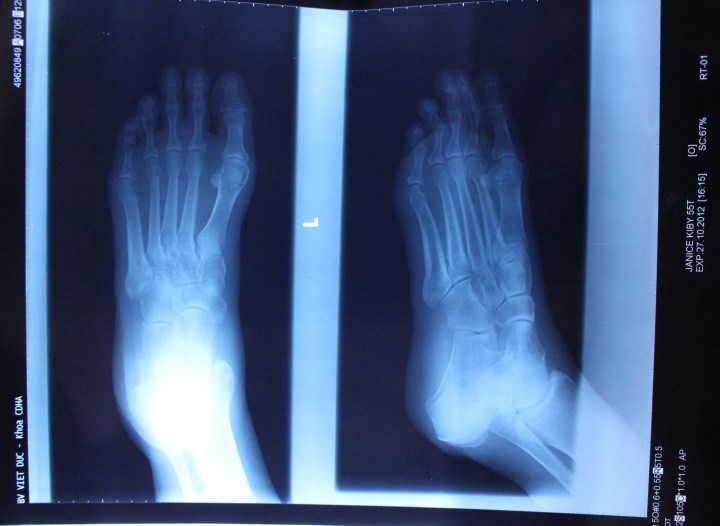

I was wheeled into the x-quang room and climbed onto the table.  The technician came in with one of those plates they put on the other side of whatever they’re x-quanging (I love that word)!  He brought out the plate they usually use for feet…..and had to go back for a bigger plate.  My feet are a bit bigger than the average foot here….sigh…..

So, that done, I met Hai Yen back out in the hall and she was complaining that she couldn’t get the ‘local’ price for me…..which, she said, would have been about a buck (I swear that’s what she said)…..  I told her, “Khong sao, khong sao” (no problem).  I knew it would be cheaper than what I’d be paying back home, anyway.  So, off to talk to the doctor to get the x-quang results and ~ yay ~ no broken bones!  I’m really relieved.  They gave me a brace for my foot which really does help.  The final cost?  About $40 USD.  Unreal.   Now it’s just a matter of time to let it heal.  That’s so easy to write…..!   Patience, Janice, patience…..phai (right)……

I was going to post a picture of my foot in the brace, but figured you’ve probably just about had your fill of pictures of my foot….. BUT!!!  I will post this picture of the x-quang: